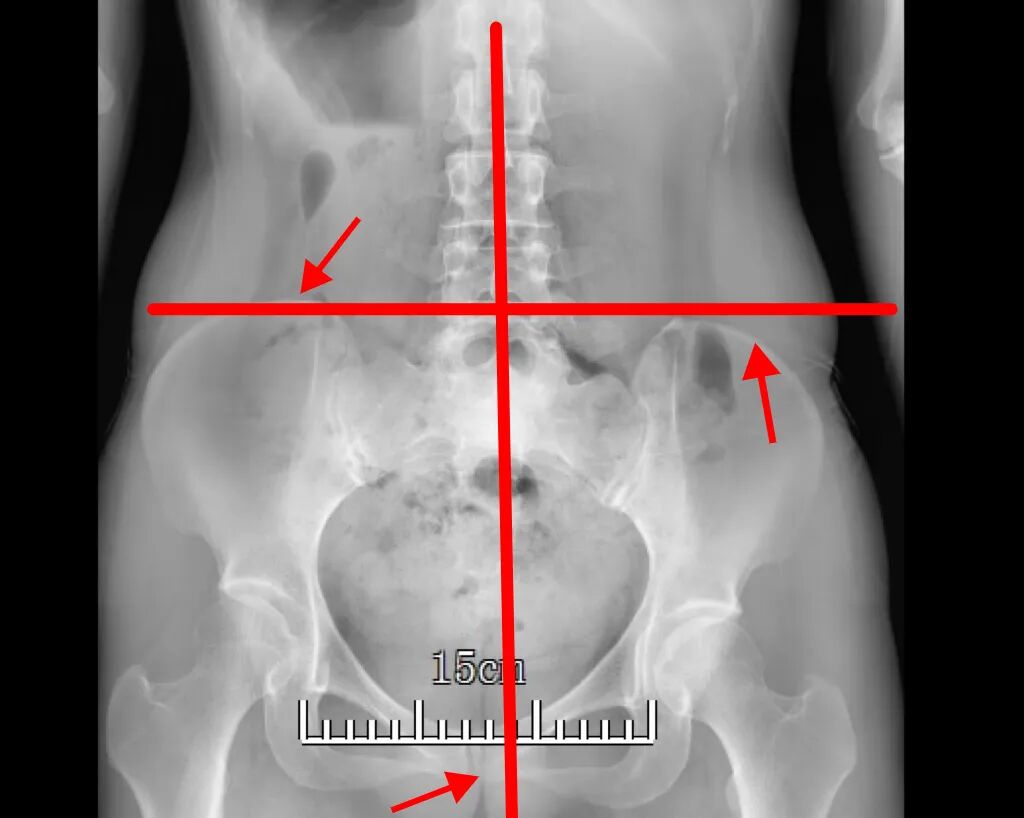

拍了片子一看,腰椎有些小毛病但并不严重,可让我吃惊的是,骨盆竟然是歪的。医生也看了、摸了我的腰部肌肉,作为检查的一部分。

我的骨盆居然歪了丨作者供图

作者描述的“骨盆歪了”,即骨盆在冠状面的不水平,称为骨盆上提/骨盆下沉。换言之,患者髂嵴的高度不水平,骨盆提升的一侧经常被称为髋关节上提。骨盆上提/下沉本质上是不对称的拉力,导致的骨盆在冠状面上的高度变化,大部分原因是一侧肌肉的过紧,也有小部分原因是另一侧肌肉的无力。一侧骨盆下沉会导致另一侧骨盆上提,反之亦然。

骨盆上提通常是由于躯干同侧侧屈肌过度激活(紧张)所致,该肌群跨腰骶关节与骨盆连接,最常累及的是腰方肌。大腿内侧的内收肌过紧,也会导致骨盆同侧上提。骨盆下沉可能是由于一侧髋关节外展肌紧张,如臀中肌。

导致骨盆上提/下沉的另一个原因是一侧的“肢体短缩”。这可能是由于一侧的股骨或胫骨比另一侧短而导致的,也可能是由于软组织不对称导致该侧肢体的高度下降,如足弓降低而导致的功能性肢体短缩。所以骨盆上提/下沉患者,需要接受下肢长度的测量,并排查是否有功能性的肢体短缩。如果原因在于下肢,那么需要进一步针对下肢的评估和治疗。各种原因引起骨盆上提/下沉时,因为身体长期处于异常的姿势,相关的肌肉会变得更加容易紧张和疼痛,这也是作者腰部疼痛的来源。

骨盆不水平的另一个影响是可能导致脊柱代偿性侧凸。所以,如果发现自己有骨盆不水平,可以去检查脊柱全长片,以排查脊柱全段的姿势问题。